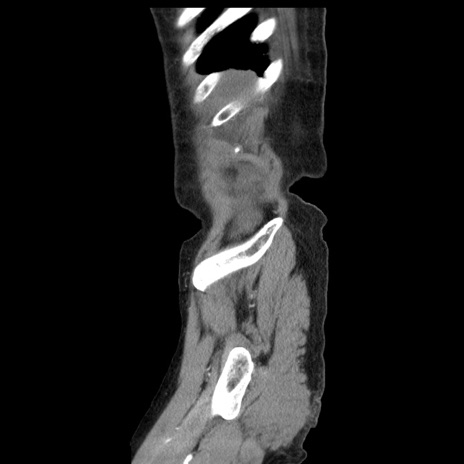

横断像

【症例】80歳代女性

【主訴】腹痛

【現病歴】8時間前から腹痛あり来院。

【既往歴】糖尿病、脂質異常症、子宮体癌にて子宮全摘術

【身体所見】意識清明・会話良好だが腹痛で苦悶様、全腹部にわたって反跳痛と圧痛あり

【データ】WBC 13600、CRP 0.14、LDH 224、CK 90